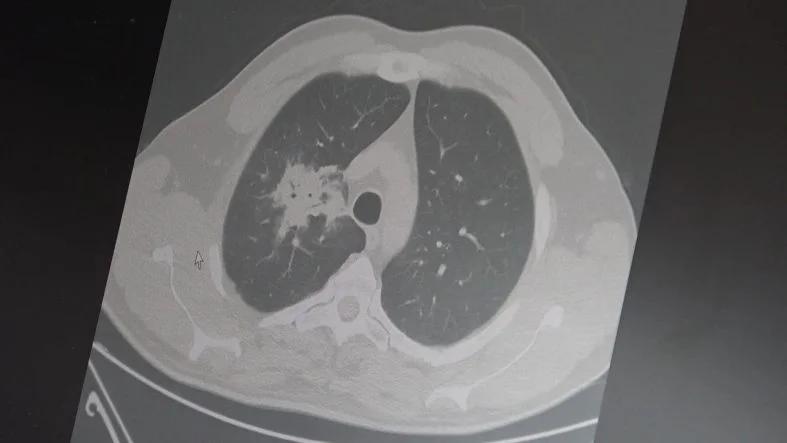

Özkaya, 100'den fazla bilimsel çalışmanın incelendiğini belirterek elektronik sigaraların özellikle akciğer ve ağız bölgelerinde kanser riskini artırabileceğine dair güçlü bulgular bulunduğunu belirtti.

2024 yılında yayımlanan bir çalışmaya da değinen Özkaya, hem geleneksel sigara hem de elektronik sigara kullanan bireylerde akciğer kanseri riskinin, sadece sigara içenlere göre dört kat daha fazla olduğunun bildirildiğini kaydetti.